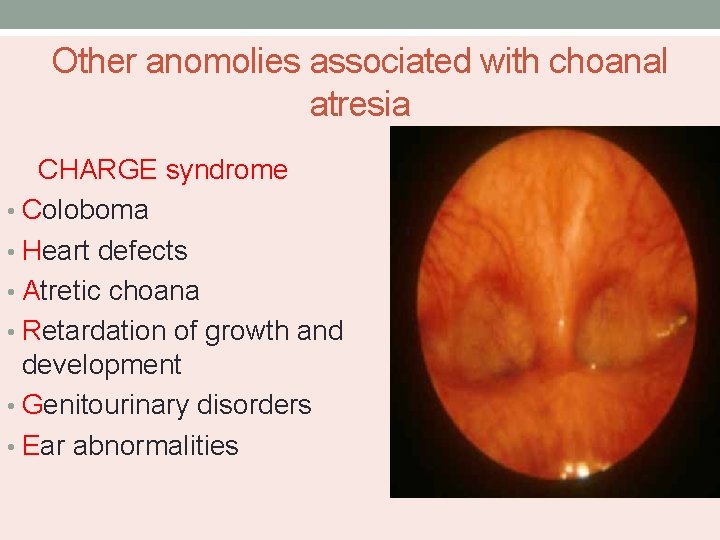

Other anomolies associated with choanal atresia CHARGE syndrome • Coloboma • Heart defects • Atretic choana • Retardation of growth and development • Genitourinary disorders • Ear abnormalities